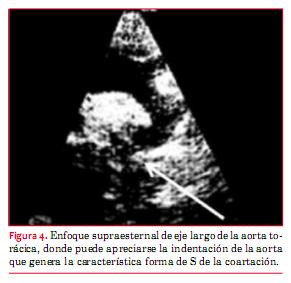

En la coartación de aorta (CoAo) posductal la morfología de la aorta es anormal en forma de S, como puede apreciarse en la figura 4. A este nivel suele observarse flujo turbulento con velocidad aumentada y gradiente que persiste en diástole (“arrastre diastólico”) (figura 5). Finalmente la aorta abdominal carece de expansión sistólica y de flujo pulsátil, registrándose, en cambio, flujo continuo (figura 6). La magnitud del gradiente registrado depende de la importancia de la coartación pero también de la magnitud de la circulación colateral que se haya desarrollado. Un gradiente sistólico máximo de 20 mmHg o superior se considera indicación para actuar sobre la misma (nivel de evidencia C)(15).